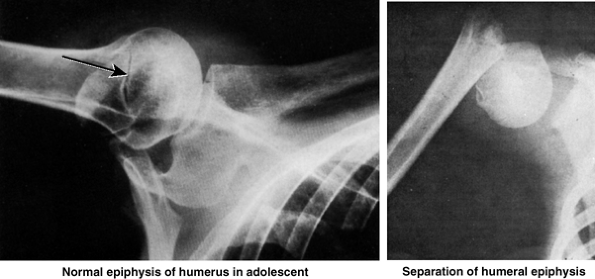

whose demineralized bones are brittle. Humeral fractures are often

result in one fragment being driven into the spongy bone of the other

fragment (impacted fracture). The injuries

usually result from a minor fall on the hand, with the force being

transmitted up the forearm bones of the extended limb. Because of

impaction of the fragments, the fracture site is sometimes stable and

the person is able to move the arm passively with little pain.

The fracture usually results from a fall on the acromion, the point of

the shoulder. In younger people, an avulsion fracture of the greater

tubercle usually results from a fall on the hand when the arm is

abducted. Muscles (especially the subscapularis) that remain attached

to the humerus pull the limb into medial rotation.